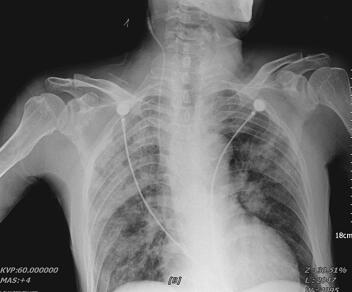

入院第2日(5月25日)22时患者出现胸闷、气喘、端坐呼吸,双肺听诊可闻及广泛湿啰音,中心静脉压18mmHg。B型脑钠肽777pg/ml。床边胸片:两肺纹理明显增多,双肺见多发片状影,密度不均(图2)。考虑出现急性左心衰竭,给予利尿、扩血管降低后负荷、控制输液量与速度,无创通气,症状逐渐缓解。

图2 入院第2日床边胸片示肺部大片状高密度影